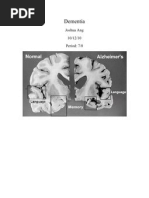

Disorders grouped under the general term “dementia” are caused by abnormal brain changes.

These changes trigger a decline in thinking skills, also known as cognitive abilities, severe

enough to impair daily life and independent function. They also affect behavior, feelings and

relationships. Dementia is not part of normal ageing. Although it can occur at any age, it’s

more common in older people.

Figure 1:Dementia